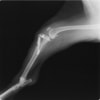

術前側面像

術前に25°であったTPAは、TPLO実施により7°に矯正されました。症例の歩行状態は良好です。